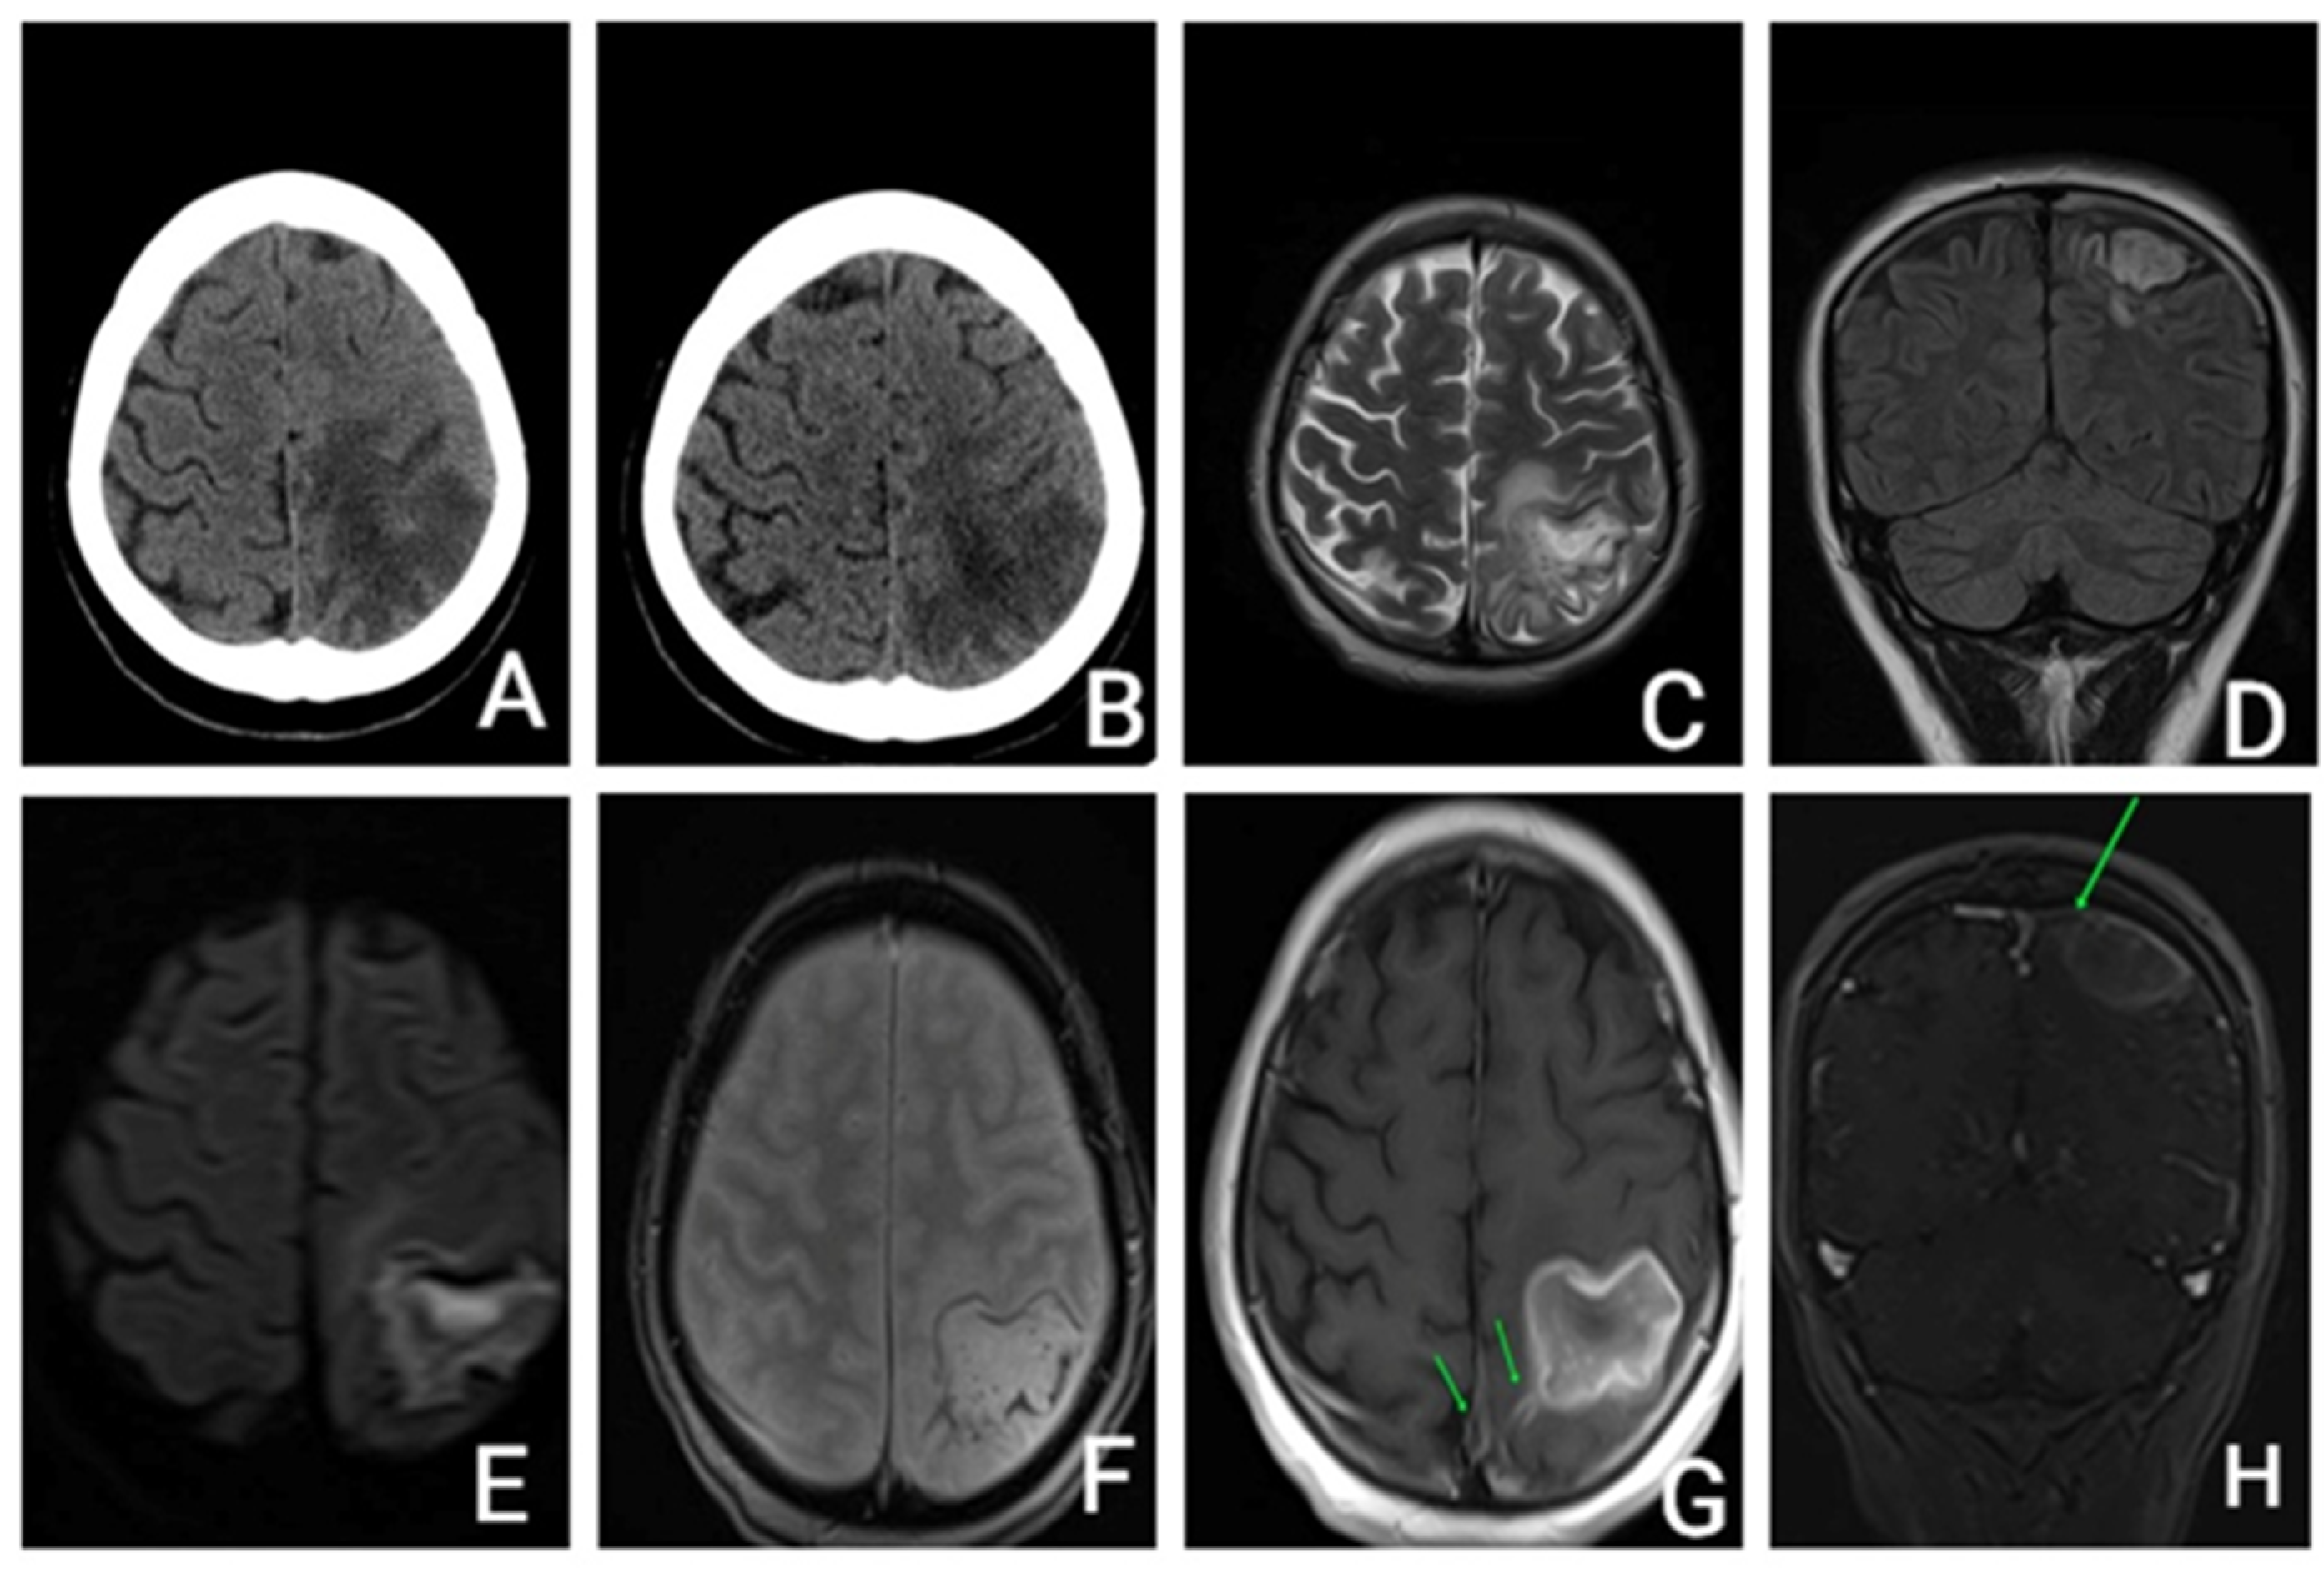

She underwent an unenhanced cerebral CT that revealed a parietal hypodensity with hemorrhagic transformation. (Figure 1).

Figure 1.

(A,B)—Unenhanced CT axial: (A)—acute parietal stroke with hemorrhagic transformation; (B)—9 days apart—Unenhanced head CT axial: subacute parietal stroke with hemorrhage resorption. (C–H): Brain MRI with and without contrast enhancement: (C)—T2 axial, (D)—FLAIR coronal, (E)—DWI axial, (F)—T2* hemo axial, (G)—T1 axial after i.v. contrast, (H)—T1 coronal after i.v. contrast. Ischemic area with hemorrhage transformation, hemosiderinic deposits mostly in periphery, central restricted diffusion and peripheral enhancement, filling defects of the sagittal venous sinus and of a cortical vein towards the affected left parietal area. CT—computer tomography; T1—weighed image; T2 weighted image; FLAIR—fluid attenuated inversion recovery; DWI—diffusion weighted imaging; T2* hemo—T2 weighted sequence.

The head CT scan, performed 9 days after admission, showed that the hemorrhage was in a resorptive stage. The diagnosis of CVT was then considered and contrast-enhanced cerebral MRI confirmed sagittal venous sinus thrombosis.

Close monitoring was performed after discharge, clinically, biologically, and radiologically. Three months after the CVT, she had completely recovered all her motor functions with the use of neurorehabilitation therapy. However, she developed symptoms of depression, for which she started receiving antidepressant medication. The brain MRI (Figure 3) showed the lesion as being chronic with the hemorrhage partially resolved at three months, with an aspect of organizing hematoma.

Figure 3.

(A–D): Unenhanced brain MRI (at 3 months): (A)—Fluid attenuated inversion recovery (FLAIR) coronal, (B)—Diffusion-weighted imaging (DWI) axial, (C)—T2* hemo axial, (D)—T1 sagittal: Chronic ischemic left parietal lesion with hemorrhagic transformation partially resolved. E-H: Unenhanced and enhanced brain MRI (at six years): (E)—FLAIR coronal, (F)—DWI axial, (G)—T2* hemo axial, (H)—T1 sagittal after i.v. contrast administration: Chronic ischemic left parietal lesion with slightly peripheral gliosis, without restricted diffusion and minimal hemosiderin peripheral deposits, without filling defect of the veins and venous sinuses.

Three years later, she underwent another brain MRI (Figure 3) that showed a chronic ischemic left parietal lesion with partial peripheral gliosis and peripheral hemosiderin deposits.

A follow-up brain MRI at six years showed the chronic lesion with no filling defect of cerebral veins and sinuses.